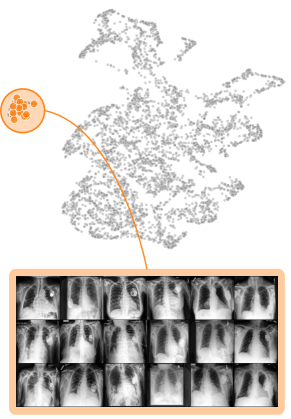

Both input and latent relevance clustering require subsequent human supervision to determine whether outlier clusters represent valid or spurious behavior. To semi-automate this process, Anders et al. [3] propose using Fisher Discriminant Analysis [37] to rank class-wise clusterings by linear separability, while Dreyer et al. [27] computes similarities between prototypes. The results of clustering approaches can serve as an initial set for bias modeling methods outlined in Sec. 3.2, which can be refined iteratively. An example outlier cluster of latent relevances is shown in Fig. 4 (top), with all samples containing the spurious band-aid concept.

Data Perspective

We first apply SpRAy in input and latent space, computing input feature importance scores using LRP summed over color channels. To obtain latent relevances, we use intermediate relevance scores in the LRP computation process after the (out of four) residual block, max-pooling over spatial dimensions to yield relevance scores for layer with channels. The clustering of pairwise cosine distances between heatmaps is shown in Fig. 6 (top left). Detected outlier clusters contain samples with spatially coherent biases, e.g., the black circle around the lesions originating from microscopes (). In contrast, clustering latent relevance scores reveals more complex, less spatially dependent clusters, as shown in Fig. 6 (top right), including the ruler artifact () and the microscope (). Compared to those in input space, the cluster for the microscope in latent space represents a more diverse high-level concept. In the input space visualization, we further highlight samples from the ruler cluster detected in latent space. Instead of forming a cluster, they spread across the entire embedding space, indicating that the bias is too complex to be detected in input space.